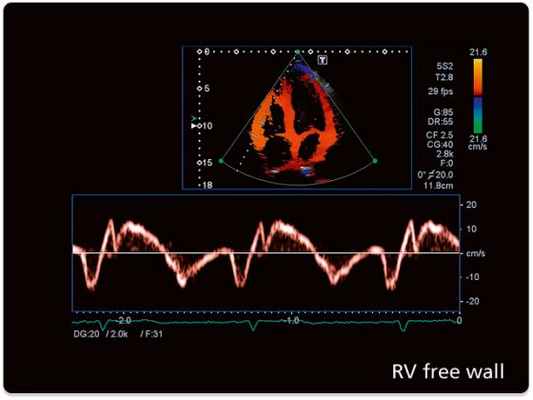

б) Скорости и интенсивности. Используя уравнение Допплера, можно непосредственно рассчитать скорость движения подвижной отражающей поверхности (рефлектора). При помощи допплер-ЭхоКГ измеряется скорость движения крови (непрерывноволновая, импульсно-волновая и цветовая допплер-ЭхоКГ), а в последнее время также и скорость движения плотных структур сердца, например, миокарда (тканевая допплерЭхоКГ в импульсно-волновом или цветовом режиме).

В случае тканевой допплер-ЭхоКГ при помощи соответствующих фильтров выделяются сигналы от плотных структур, а сигналы от крови подавляются: если эритроциты довольно слабо отражают ультразвук, но движутся с относительно высокой скоростью (до 1,5 м/с через отверстие аортального клапана у здорового человека) и, таким образом, вызывают значительное допплеровское смещение, то миокард и другие структуры сердца характеризуются относительно высокой отражающей способностью, а скорости, наоборот, достигают значений не более 15-20 см/с в базальных отделах боковой стенки левого желудочка.

Тканевый допплер (Tissue Velocity Imaging). Принцип данного метода основан на картировании направления движения тканей определенным цветом. Таким образом красным цветом обозначают движение к датчику, синим - от датчика. Изучая направления движения стенок левого и правого желудочков в систолу и диастолу с помощью TVI можно обнаружить скрытые зоны нарушения локальной сократимости. Совмещение двухмерного исследования в режиме TVI с M-модальным увеличивает точность диагностики.

Тканевой импульсный допплер (Pulsed Wave Tissue Velocity Imaging). Позволяет оценить графически характер движения стенки желудочков в конкретной данной точке. Выделяют систолический компонент, ранний и поздний диастолический компоненты.Данный вариант допплера позволяет проводить картирование миокарда и увеличивает точность диагностики у больных с ишемической болезнью сердца.